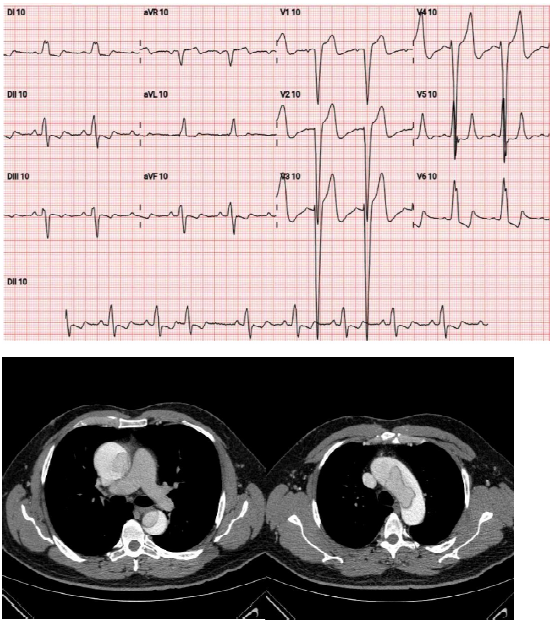

Sr. Manoel, 65 anos, procura pronto-socorro e relata forte dor retroesternal há 50 minutos e histórico de hipertensão arterial. Ao exame clínico, as auscultas pulmonar e cardíaca estão normais, pressão arterial de 170x 100 mmHg, frequência cardíaca de 76 bpm, frequência respiratória de 19 irpm, temperatura de 36,4º C e saturação de 97%. Foram também realizados os exames abaixo: enunciado 963886-1 Qual a conduta a ser adotada para esse caso?